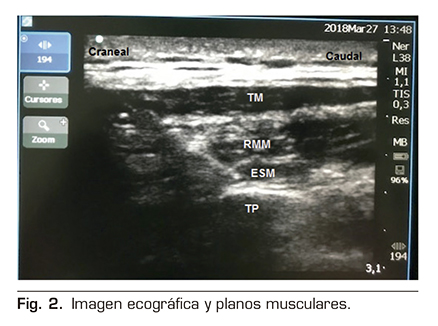

Se le realizó un bloqueo ecoguiado ESPB con colocación de catéter para analgesia continua posterior. Para ello, se colocó al paciente en posición de decúbito lateral derecho, y se procedió a la preparación de la zona de punción con povidona yodada, colocación de campo estéril y elección de sonda ecográfica lineal de alta frecuencia. Se identificó la apófisis espinosa de la 6.ª vértebra torácica y a una distancia de 3 cm lateral se identificó el proceso transverso de la misma. En la imagen ecográfica, visualizamos el plano subcutáneo y varios grupos musculares que de superficial a profundo corresponden con el músculo trapecio, romboides y erector de la columna, todos ellos sobre la apófisis transversa vertebral (Figura 2).